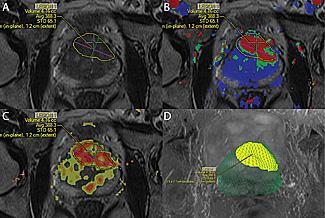

MRI technology was used to identify and locate a probable tumor (outlined in yellow) during a targeted prostate biopsy for a patient who had previously had multiple negative biopsies but had persistently high PSA levels. Resulting biospy confirmed presence of high-grade cancer.

For patients, the only added step to the prostate examination is the addition of MRI imaging, which occurs in a separate visit in advance of the biopsy exam. Working with David Karow, M.D., Ph.D., a UC San Diego Health System radiologist, Parsons uses sophisticated new tools and software – DynaCAD for Prostate with the UroNav fusion biopsy system – to combine the MRI with real-time, ultrasound-guided biopsy images in the clinic, resulting in what he calls a 3-D road map of the prostate.